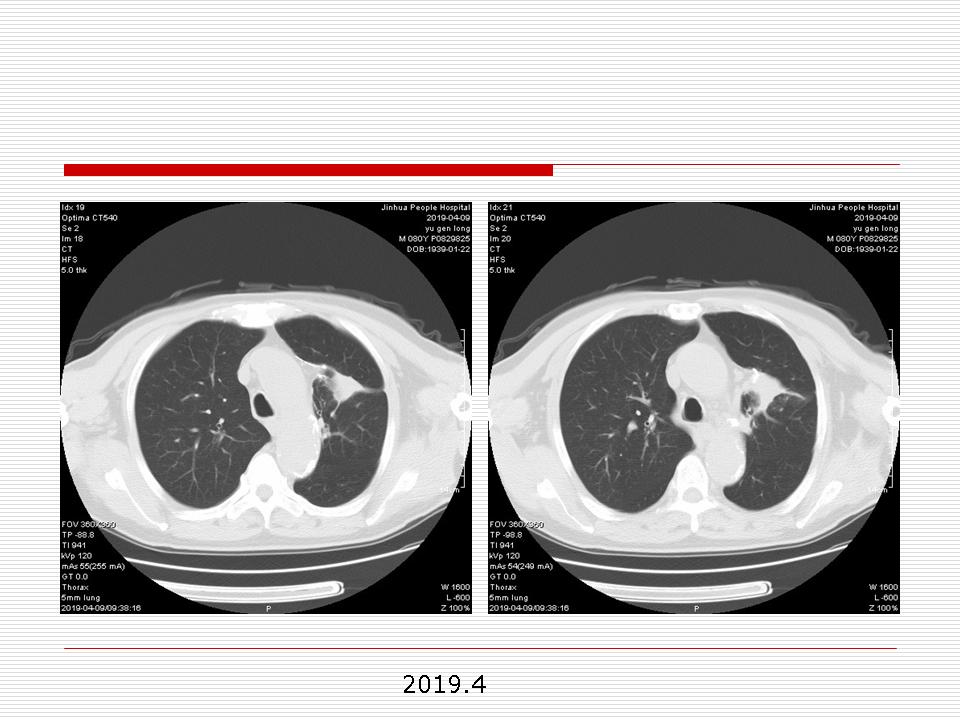

肺部阴影永恒且最重需要鉴别的是:到底是炎症还是肿瘤?但临床的病例中的影像表现难以界定或有些肿瘤特征,同时又有些炎症特点是非常常见的情况。作为临床医生我们怎么去总结分析,并找到之所以是炎症或之所以是肿瘤的细微差别或特点非常重要,也非常有用。2019.12.7浙江省2019年胸心外科学学术年会在宁波召开时,我的临床病例分析与经验总结<那些像肺癌的炎症与像炎症的肺癌>获得在大会交流的机会,以下为该PPT的内容,与你分享,希望对同道有益,有借鉴与启迪。若有探讨与进一不完善的建议,欢迎文末留言讨论: